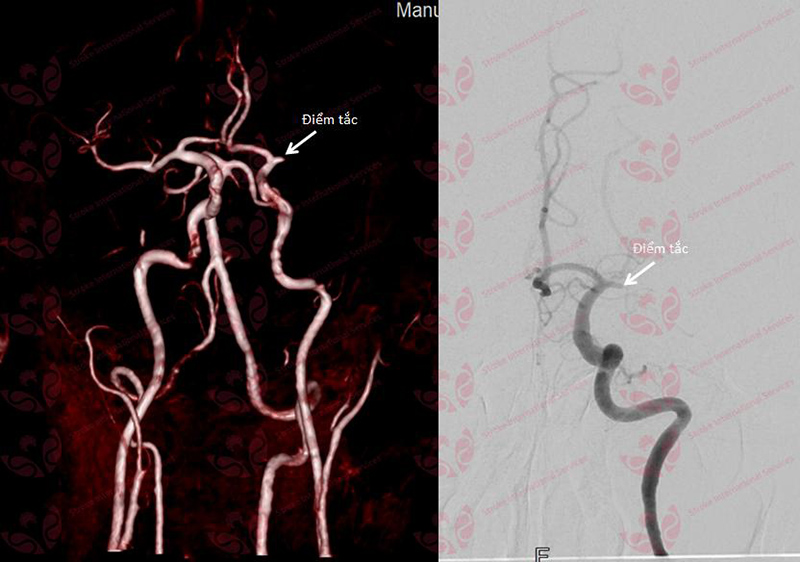

Hình ảnh tắc mạch máu não